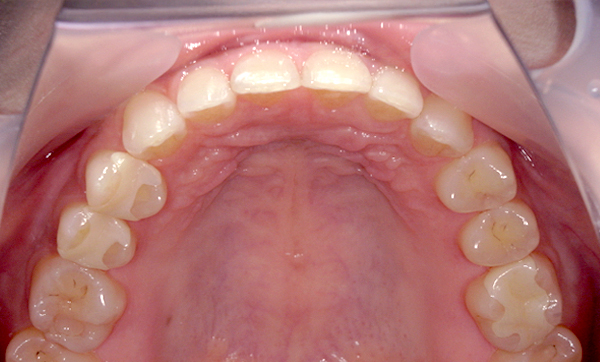

| 治療前 | 治療後 |

|---|---|

|